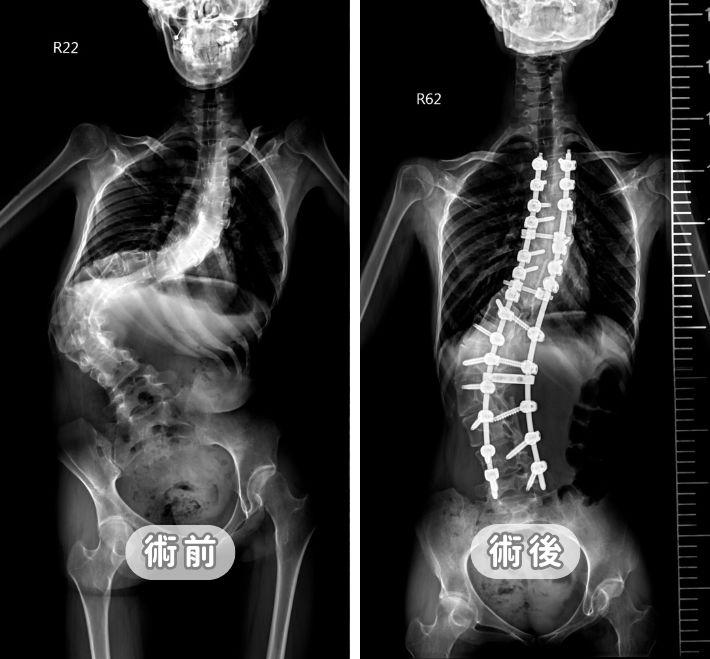

2026脊椎側彎手術全攻略:從治療黃金時機到微創技術,醫師詳解安全矯正關鍵

脊椎側彎一定要開刀嗎?張建鈞醫師深度解析青少年與成人手術指標。引進 O-arm 3D 導航系統,將誤差降至 0.1cm 以下,大幅提升安全性。本文詳解微創術式、鋼釘費用、恢復期與術後運動常見問答,助您在精準醫療下找回挺拔人生。